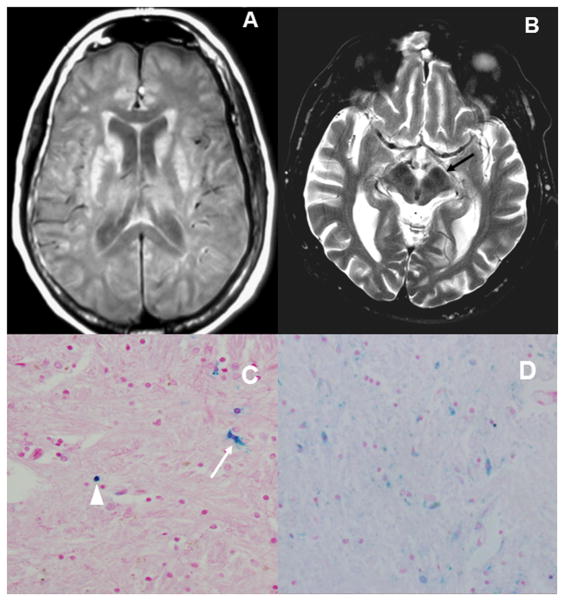

Extensive bilateral T1-W hyperintensities and T2-W hypointensities in the basal ganglia and thalamus were observed in the female patient; whereas these findings were present but subtle in the male subject (Figure 2).

Figure 2.

A) Axial T1W MRI in case 2 shows hyperintensities in both caudate nuclei and putamen B) Axial T2W MI in case 1 shows prominent hypointensites in the red nuclei and substantia nigra (arrow); these findings suggests brain deposition of iron/metal in both cases. C) Histopathology via Perls stain of case 2, confirmed astrocyte cytoplasm iron deposits (arrow) and iron in neuronal spheroids (arrowhead). D) Perls stain showing more pronounced iron deposits in case 1.

Postmortem examination of the brains was consistent with corticobasal degeneration in both subjects. Case 1 showed glial tau-positive inclusions, neuronal-tau positive inclusions, astrocytic plaques, scarce swollen (achromasic) neurons in the temporo-parietal and occipital cortex; but frequent achromatic cells were observed in the globus pallidus interna and externa. There was surface-layer spongiosis. Mild asymmetric inter-hemispheric atrophy was observed, more prominent in the right frontal lobe. Marked Perls staining of neuronal spheroids and astrocyte cytoplasm demonstrates abnormal iron deposition (Figure 2) [16]. Staining was in excess of Case 2, showed scattered tau positive inclusions in neurons and glia in the basal ganglia and thalamus. Marked diffuse gliosis was also noted in these areas. Rare ballooned neurons were observed in the parietal lobes. There was marked diffuse cortical atrophy, more prominent in the right parietal lobe. Both cases showed moderate pigment incontinence in the substantia nigra, without any Lewy bodies. Neuropil threads were seen in the gray and white matter of left (sparse) and right (moderate) frontal lobes, gray, including primary motor cortices, and white matter on fronto-parietal cuts (numerous, more prominent on the right), and sparsely in the temporal and occipital lobes. Astrocytic plaques, a hallmark of CBD pathology [17], were seen in the right frontal cortex. Coiled bodies, seen in both PSP and CBD, were seen occasionally in the gray and white matter of the parietal lobes, and rarely in the temporal lobes. Neuronal spheroids and astrocyte cytoplasm were positive on Perls staining (Figure 2).